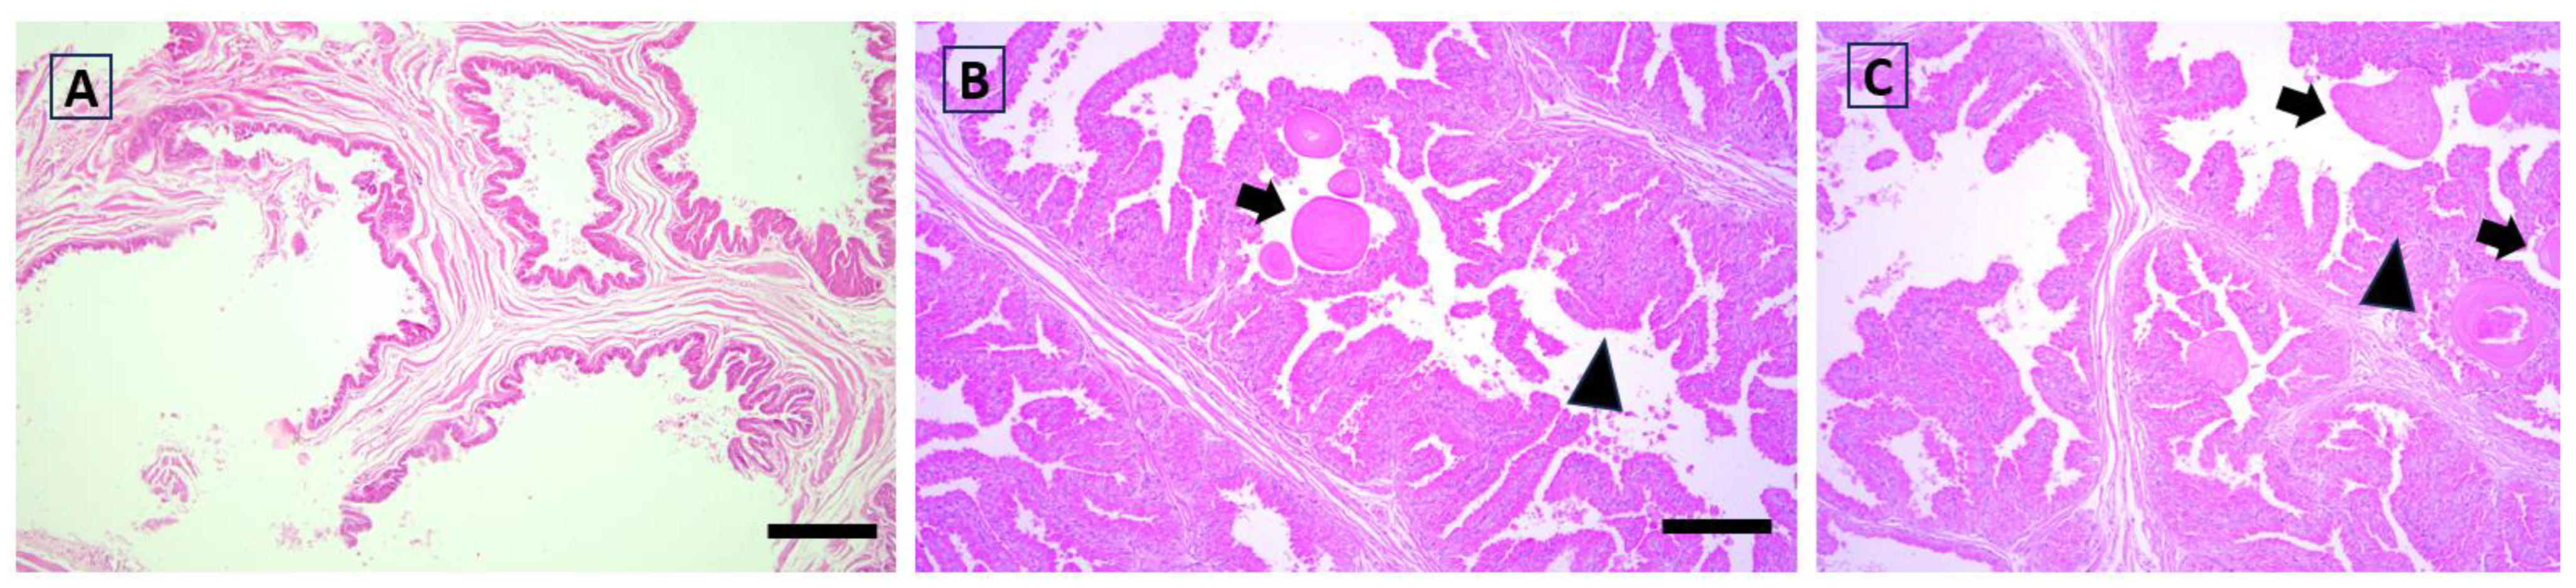

3.4. Histological Analysis